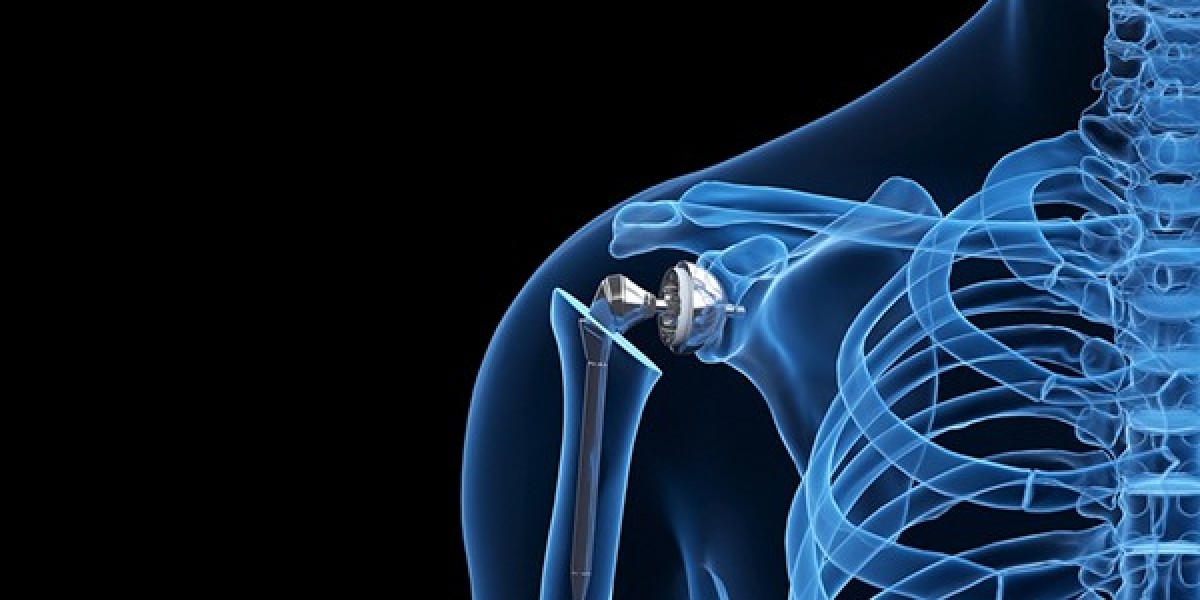

Reverse shoulder replacement is an advanced surgical procedure used to treat severe shoulder arthritis combined with rotator cuff damage. In a normal shoulder, the ball of the joint is at the top of the upper arm bone and fits into the socket of the shoulder blade. In this procedure, the structure is reversed—the ball component is attached to the shoulder blade, and the socket is placed on the upper arm bone. This design allows the deltoid muscle to power the arm instead of the damaged rotator cuff, helping restore movement and reduce pain.

This surgery is commonly recommended for patients with rotator cuff tear arthropathy, complex fractures, failed previous shoulder surgeries, or severe joint degeneration. An experienced Orthopedic surgeon in Guntur carefully evaluates imaging tests, pain levels, and mobility before suggesting this procedure. Consulting a qualified Orthopedic doctor ensures accurate diagnosis and a personalized treatment plan based on the patient’s age, activity level, and overall health.

The surgery is performed under anesthesia and typically takes a few hours. After surgery, patients undergo structured rehabilitation to regain strength and flexibility. Choosing a well-equipped Orthopedic hospital in Guntur is important for safe surgery, advanced technology, and comprehensive post-operative care. With proper treatment and physiotherapy, most patients experience significant pain relief and improved shoulder function, enabling them to return to daily activities with better comfort and mobility.